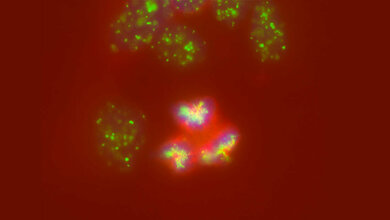

Doch auch bei der Diagnostik geht es mit Riesenschritten voran. Neben den neuen Möglichkeiten in der Bildgebung ist hier beispielsweise Liquid Biopsy ein Schlagwort. Die Nukleinsäureanalytik zum Nachweis von Tumorzellen und Tumor-DNA sorgt für Furore.